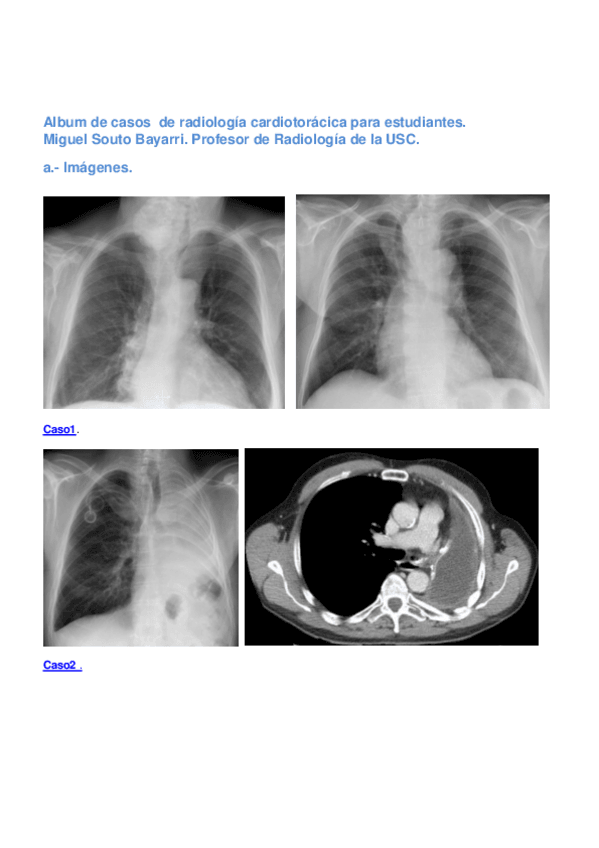

He publicado nuevos examenes de 3º Radiología I: Album-de-casos-de-radiologia-cardiotoracica-para-estudiantes.-Miguel-Souto-Bayarri.-Profesor-de-Radiologia-de-la-USC..pdf

42 páginas